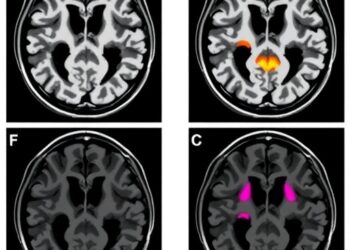

In a groundbreaking study spearheaded by Dr. Kazuhide Asakawa at the National Institute of Genetics in Japan, researchers have harnessed the power of single-cell–resolution imaging within transparent zebrafish models to probe the cellular mechanisms behind motor neuron vulnerability in ALS. This innovative approach allowed them to observe, in unprecedented detail, the physiological status and stress responses of individual spinal motor neurons in a living organism, linking structural properties with cellular dynamics.

The team’s observations reveal that large spinal motor neurons, tasked with generating powerful body movements and notably susceptible in ALS pathology, endure an inherent and continuous burden related to protein and organelle degradation. These neurons consistently exhibit elevated basal activity in three critical cellular pathways: autophagy, proteasome-mediated degradation, and the unfolded protein response. Together, these mechanisms constitute the cell’s principal modalities for maintaining protein and organelle quality control, suggesting that large motor neurons are persistently engaged in managing extensive proteostatic stress.

Further, the use of transparent zebrafish as a vertebrate model for real-time, single-cell analysis underscores the transformative potential of advanced imaging techniques in neuroscience. The capacity to visualize protein degradation dynamics within living neurons may catalyze discoveries across multiple neurodegenerative disorders characterized by proteostasis imbalance.

Image Credits: Kazuhide Asakawa, National Institute of Genetics